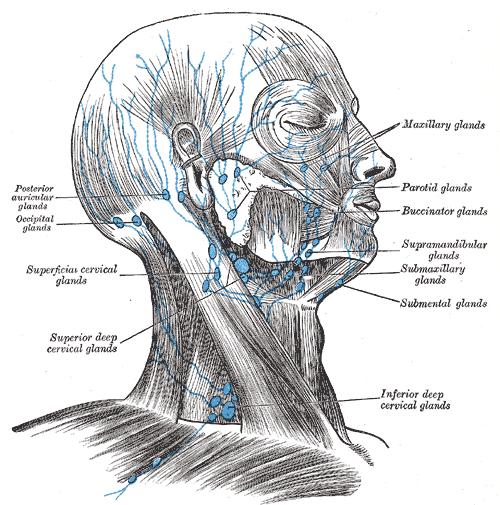

Lymphatic system

總圖

Nodes

Face

- Maxillary

- Buccinator

- Supramadibular